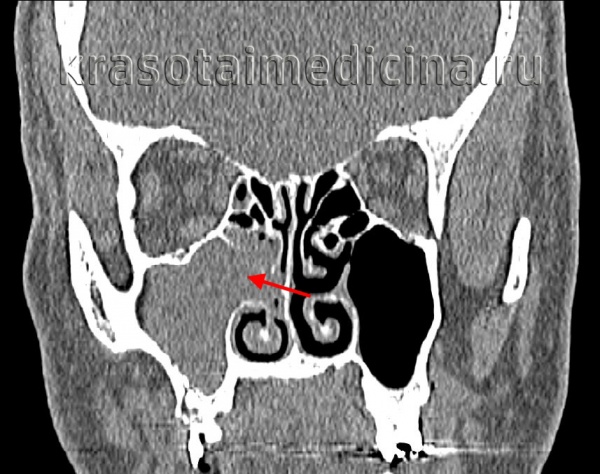

- Рентгеновское исследование ППН. Для оценки степени разрастания полипов носа проводится КТ околоносовых пазух. КТ-исследование в обязательном порядке проходят пациенты, которым предстоит хирургическое лечение полипов носа, поскольку результаты компьютерной томографии позволяют хирургу заранее определиться с объемом операции и разработать соответствующую тактику ее проведения. При отсутствии возможности для использования в диагностике компьютерной томографии состояние пазух исследуют при помощи рентгенографии.

- Томографические исследования. Для оценки характера разрастания полипов применяют КТ или МРТ околоносовых пазух. С их помощью также можно выявить анатомические дефекты (искривление перегородки, кисты в синусах, сужение и деформацию носовых ходов).

- КТ носовых пазух. Компьютерная томография выполняется для определения распространенности образований, оценки анатомического строения пазух и обнаружения дефектов. Исследование проводится перед хирургическим вмешательством для определения объема операции.